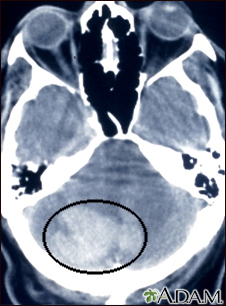

Intracerebellar hemorrhage - CT scanBackIntracerebellar hemorrhage - CT scanIntracerebellar hemorrhage shown by CT scan. This hemorrhage followed use of t-PA. E-mail FormEmail ResultsName:Email address:Recipients Name:Recipients address:Message: